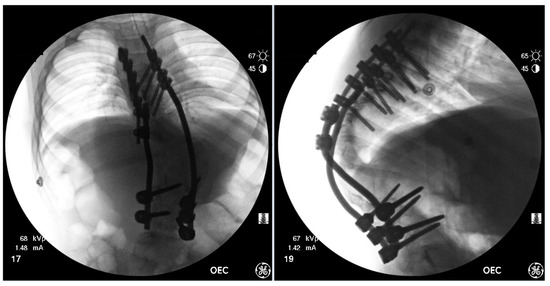

Figure 8.

AP & Lateral fluoroscopy images of the final instrumentation & deformity correction.

Strategic distraction, compression and de-rotation were used to achieve further correction–reduction of the kyphosis–slowly, using the rod exchange maneuver multiple times with temporary rods. Once substantial correction was achieved, these were exchanged with definitive rods placed from T5 to L4. After fine-tuning the correction, the MEPs did improve with tibialis anterior MEPs returning on both sides. Two cross links were placed over the vertebral body resection site. With the final correction achieved, further bone graft was applied across the posterolateral gutters, the facet joints and the corpectomy defect site, and the wound was closed (Figure 8).